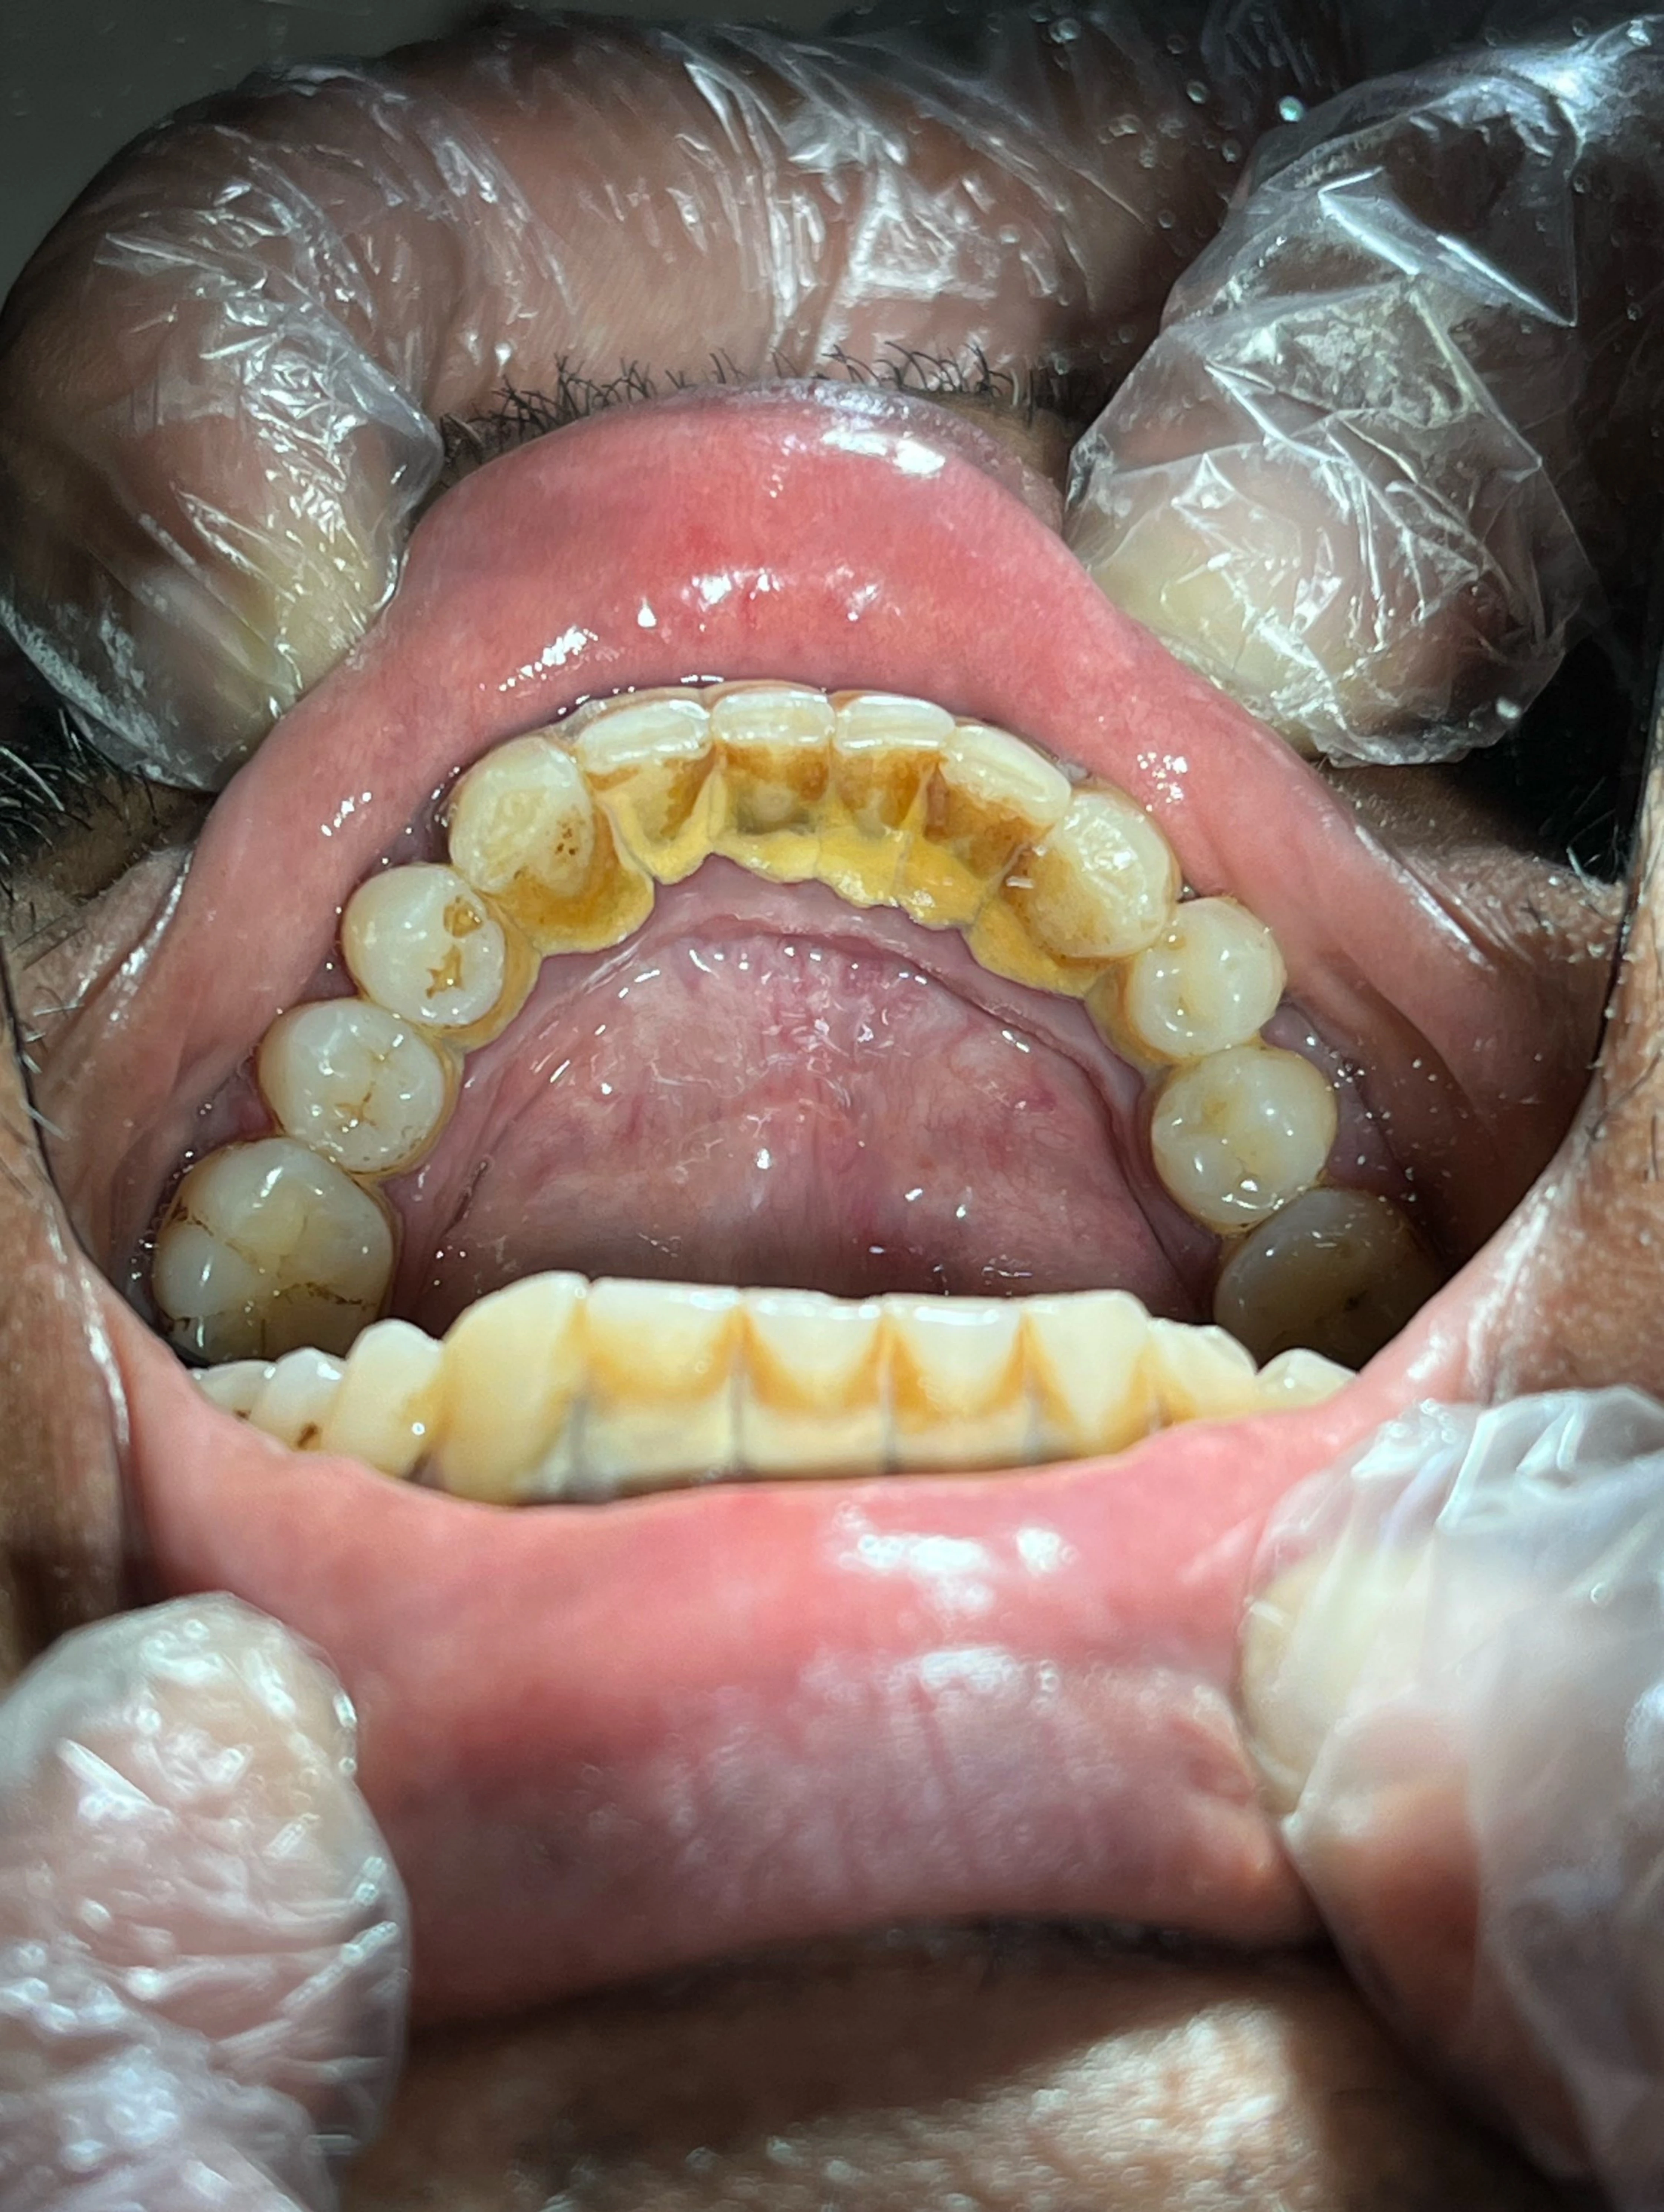

Scaling and polishing is a professional dental cleaning procedure designed to remove plaque, tartar (hardened plaque), and stains from your teeth.

Scaling involves the careful removal of plaque and tartar from the tooth surface and below the gum line using specialized dental tools. These deposits cannot be removed by regular brushing alone.

Polishing, on the other hand, is the final step where the teeth are smoothed and polished using a special paste. This not only makes your teeth feel clean and shiny but also helps prevent future plaque buildup.

Together, these steps leave your teeth cleaner, healthier, and visibly brighter.